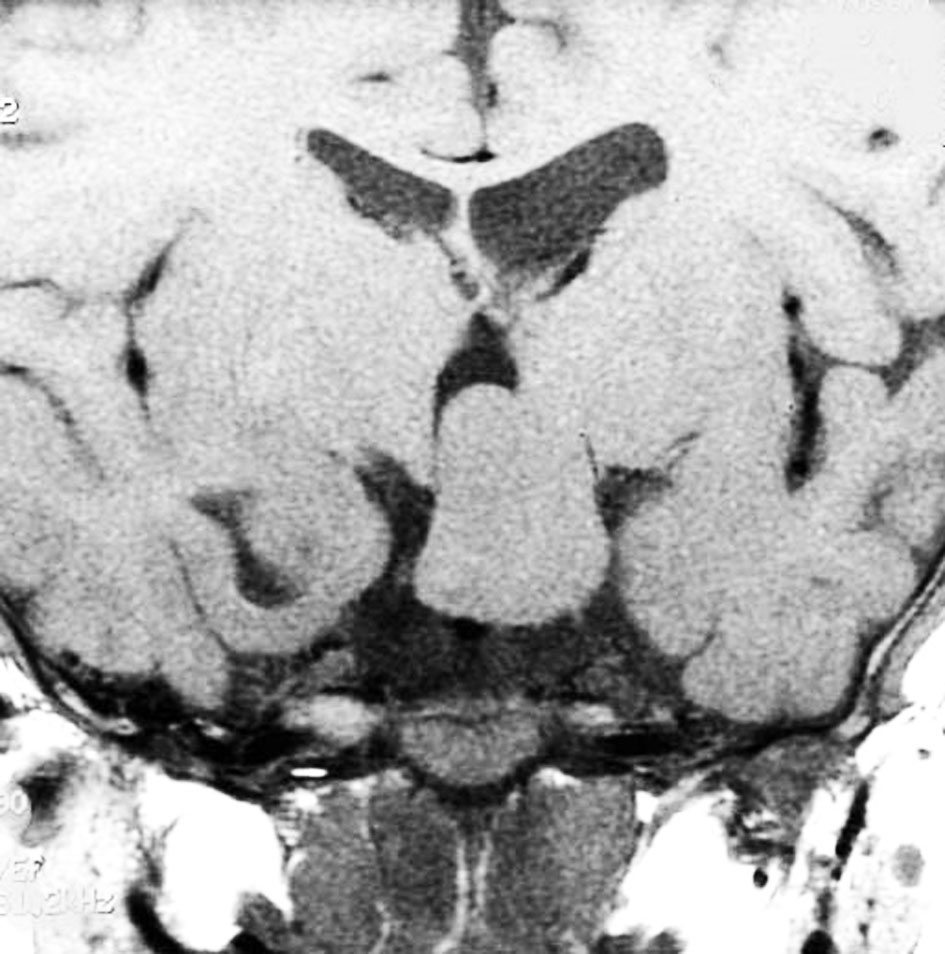

小さな典型的な視床下部過誤腫

無症候で発見されたpedunculated typeです。視床下部の底面からぶら下がるようにしてあります。左のCISS画像で形がよくわかります。中央のT1では灰白質と等信号です。右のT2では高信号となっています。

乳頭体(矢印)からは離れているタイプです。ですから笑い発作を生じません。右側のガドリニウム増強画像ではまったく増強されていないのが特徴です。